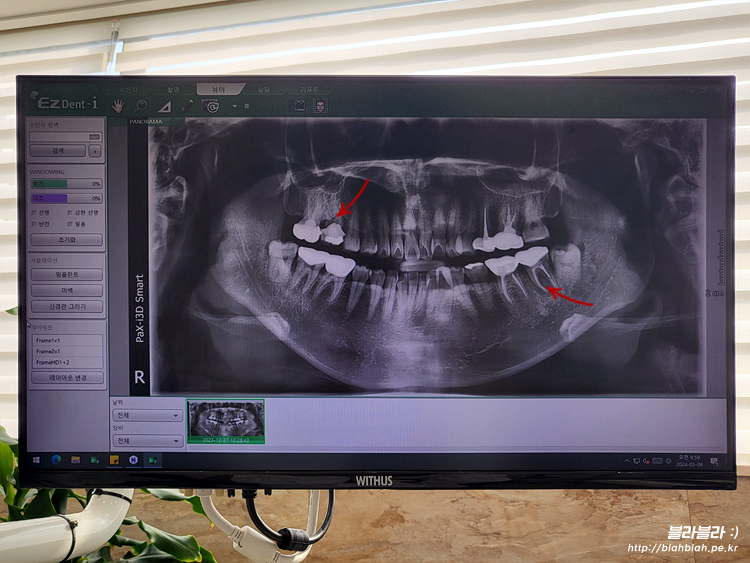

새로 방문한 치과에서 파노라마 사진 찍고

치주과 원장님과 만났습니다.

보시자마자 치아상태가 별로 좋지않고

제가 봐달라고 말씀드린 2군데 모두 임플란트행 ㅠ_ㅜ